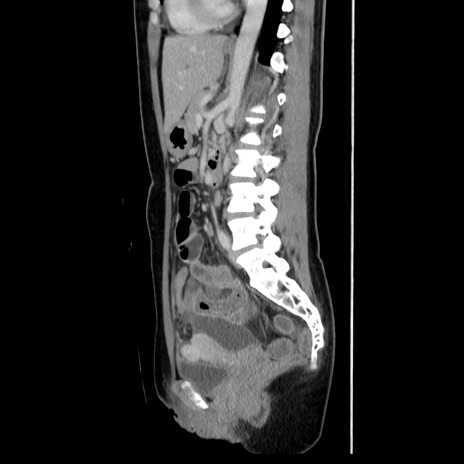

症例39(矢状断像)

【症例】40歳代女性

【主訴】上下腹部痛

【現病歴】2日目から下腹部痛あり。夜間は痛みで眠れなかった。昨日より上腹部痛と下痢が出現。臥位で痛みは軽快したため、休んでいた。本日になって臥位でも立位でも痛みが強くなってきたため救急要請。

【既往歴】子宮内膜症

【身体所見】部:平坦・軟、左上下腹部に圧痛あり、反跳痛あり。

【データ】WBC 21800、CRP 26.78

CT